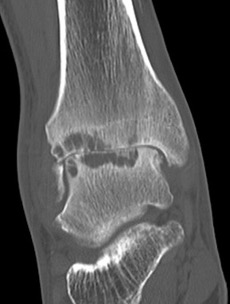

CT

Small anterior tibial spur

Large cysts in patient with ankle OA